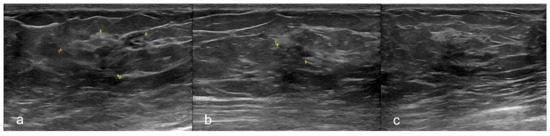

2. Case Report